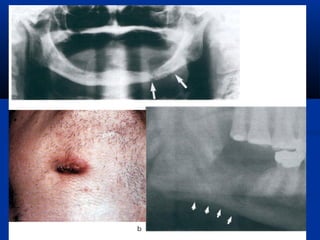

Life Threatening Infection

Intraoral infection with a skin fistula

 Scaring and sinus & fistulaScaring and sinus & fistula

formation.formation.